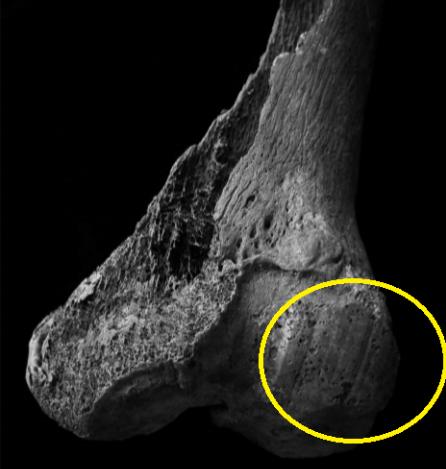

个子高在现代可能是件好事,这暗示着营养充足或者基因良好,不过太监们的高个子,却要付出病痛的代价。目前出土的太监骨骼内部,许多都出现了大量海绵样网状结构,重量也比正常骨头轻——这是典型的骨质疏松症状,也暗示了他们可能要承受某些身体上的痛苦,比如,如果上了年纪,腰椎会因为骨质疏松,出现压缩性骨折或者骨刺,这会导致他们生前背痛,严重的甚至会弯腰困难、下肢麻木[4]。

北京市发掘出的明代太监墓,其中一具人骨的左膝盖关节表面显示出“象牙面”。这是当软组织因年龄、劳动或者疾病原因消磨殆尽后,骨骼之间相互磨损而产生的光滑面,也代表个体生前可能要忍受膝痛。根据他的职业,不免联想到,这是因日常跪地动作在骨骼上留下的痕迹。